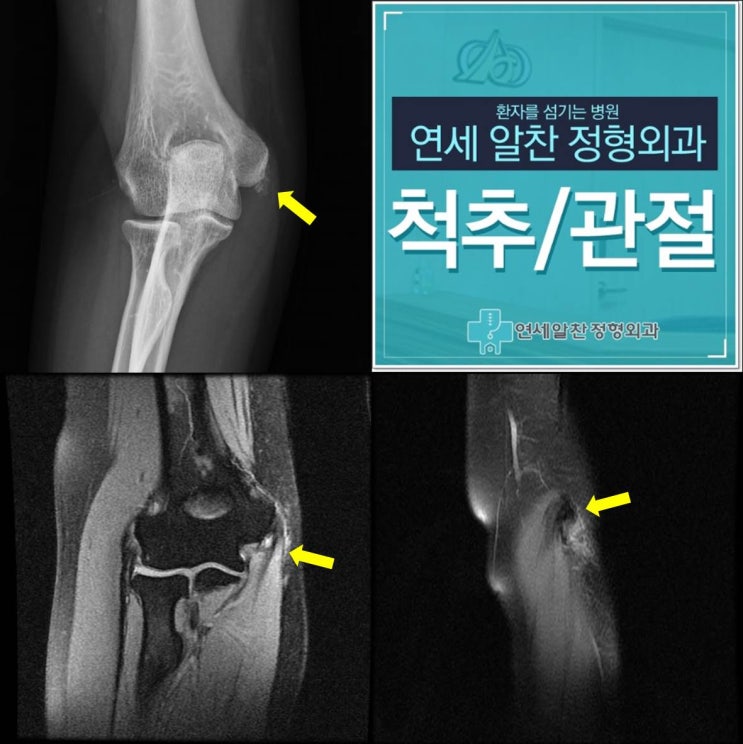

슬개골 탈구 및 슬개연골 손상에서 관절경적 치료 및 슬개연골 고정술의 결과

26세 여자환자로 넘어지면서 발생한 무릎 통증을 주소로 본원으로 내원하였다. 이학적 검사상 fluid collec...